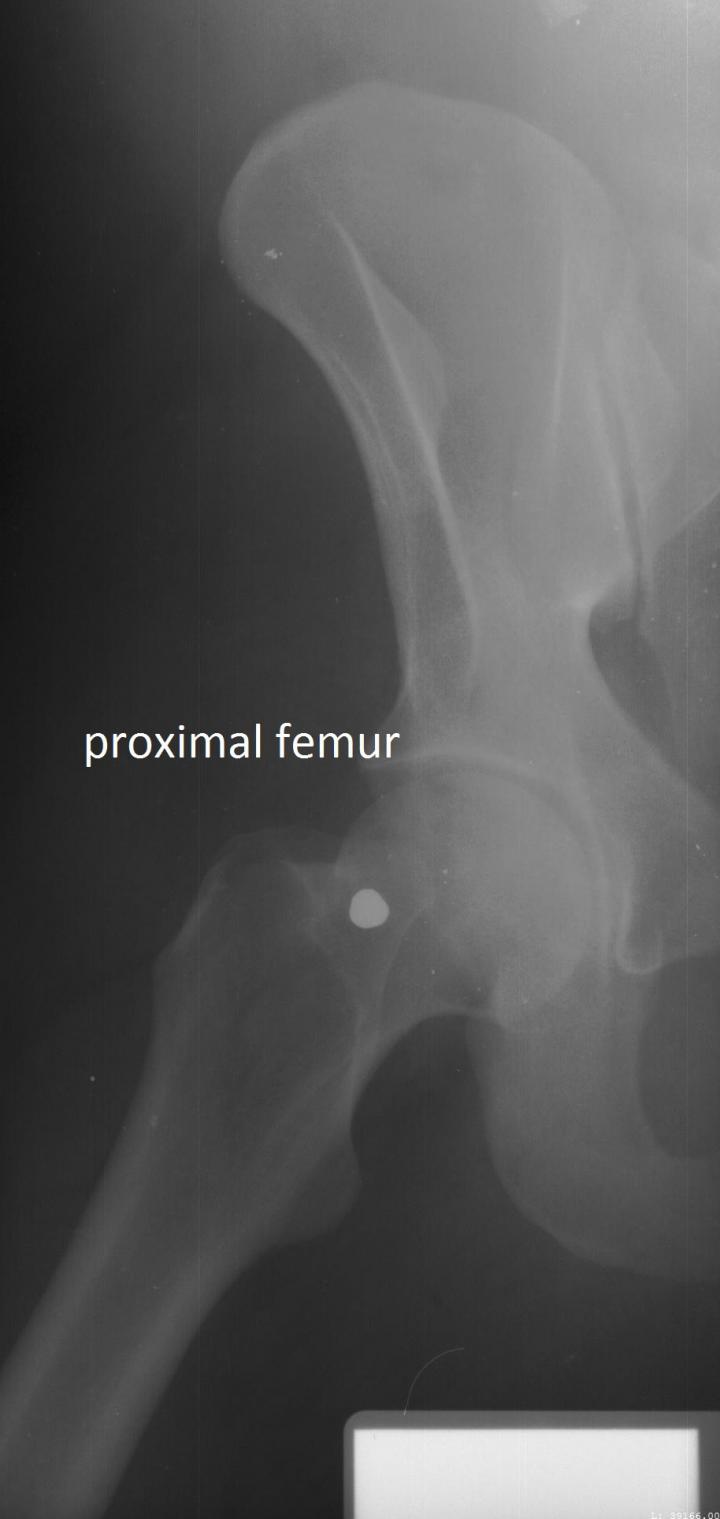

Forensic researchers have for the first time established science-based standards for identifying human remains based on X-rays of an individual's spine, upper leg or the side of the skull.

The researchers compared ante mortem and post mortem lateral craniofacial (side of the skull) X-rays for 20 individuals, and did the same for X-rays of the vertebral column (spine) for 50 individuals, and X-rays of the proximal femur (upper leg) for 23 individuals. The researchers used these evaluations to develop location-specific standards for each skeletal region. The researchers focused on these skeletal regions because they are among the most frequently X-rayed in a clinical setting.

For example, a side X-ray of the skull could be used to identify a body with 97 percent certainty and a 10 percent misclassification rate based on as few as two specific traits - as long as there were no inconsistencies in the shapes of the skull X-rays. Cervical - or neck - vertebrae performed even better. These could provide greater than 98 percent certainty and a 7 percent misclassification rate based on a single trait.